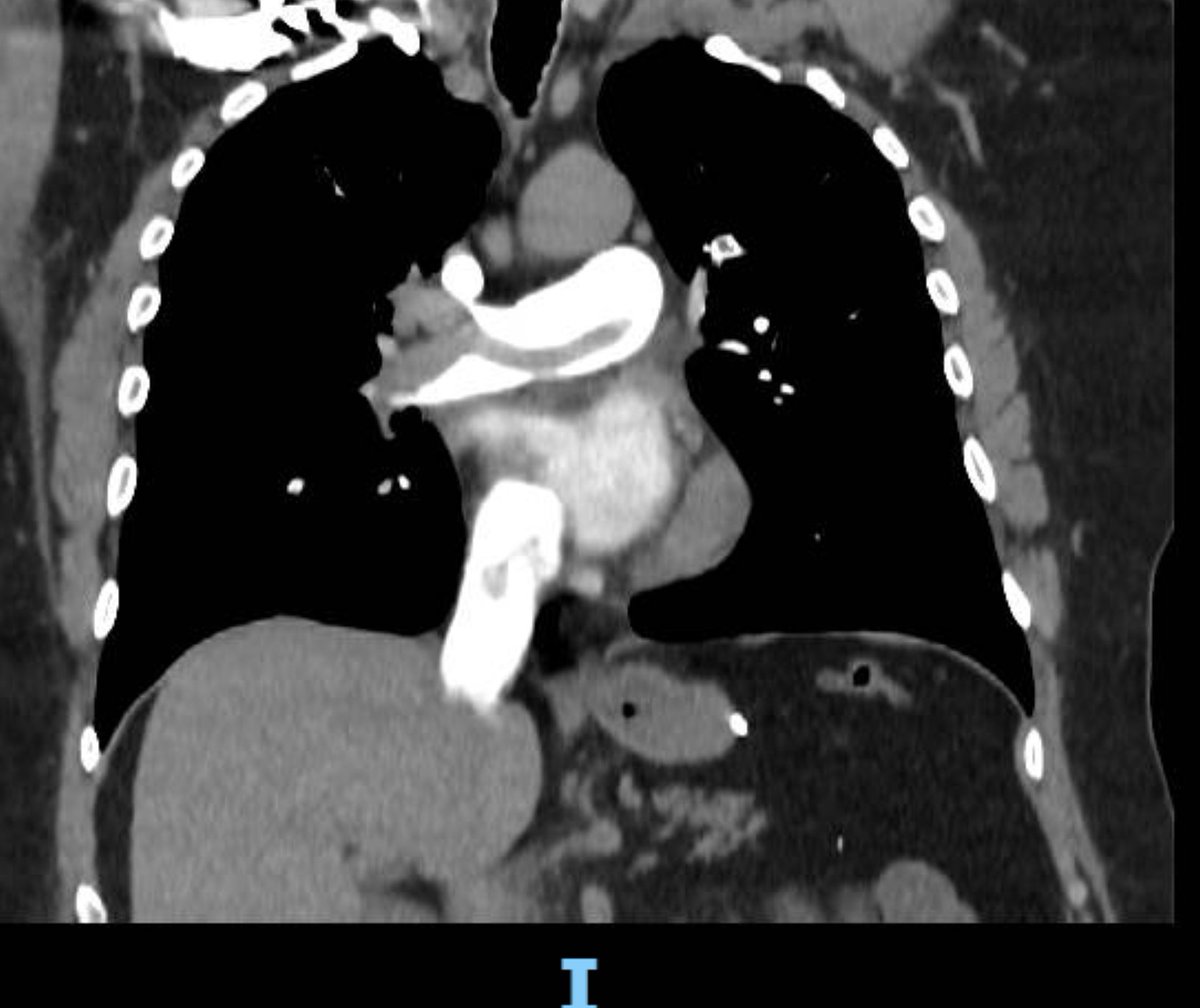

Should we perform echocardiography for all STEMI patients? 55 A 55-year-old man with severe chest pain, high blood pressure, and STEMI, activated primary PCI. Point-of-care echo showed below @POCUS @HoosierPocus @EchoCases

dilated ascending aorta with a clear flap, arch of aorta, and descending aorta down to renal arteries. The plan changed to CT aortography, and the patient was taken to the cardiac OR. The whole aorta was repaired successfully

Arterial aneurysms are among the rare vascular manifestations of HIES. We present a case of a 17-year-old girl who had a known history of HIES since childhood. She had a large thoracic descending aortic aneurysm, which required surgical repair to prevent complications

Hyperimmunoglobulin E syndromes (HIES) are a heterogeneous group of primary immunodeficiencies sharing manifestations including recurrent lung infection and significantly raised serum levels of immunoglobulin E.